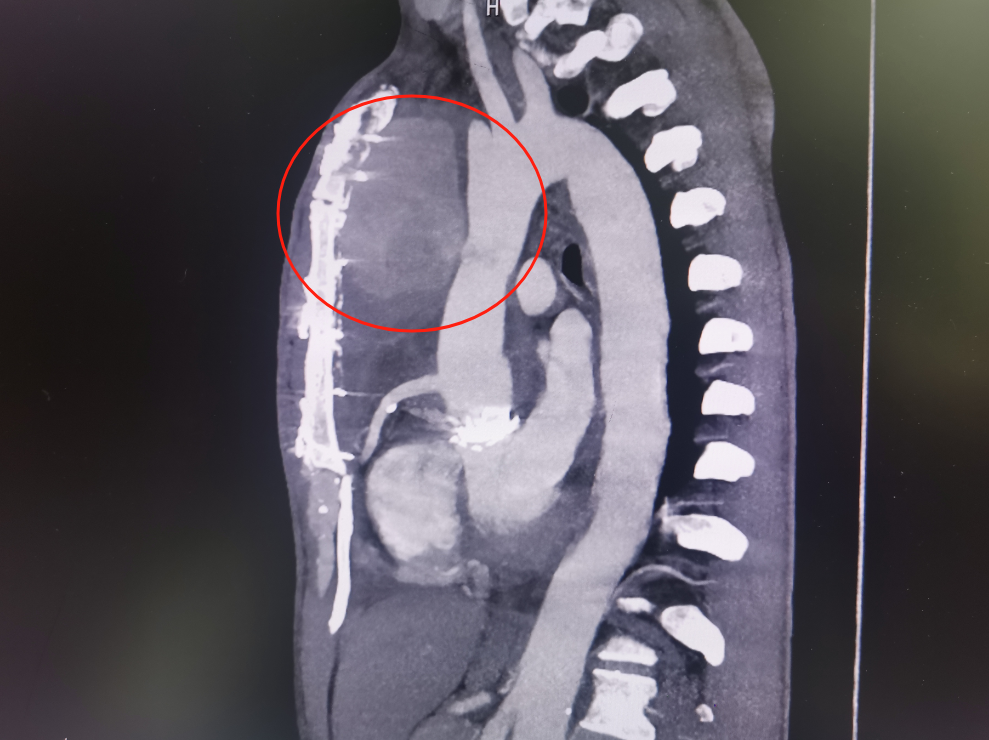

经检查,林先生系升主动脉假性动脉瘤破裂出血,也就是连接心脏最粗的一根动脉血管破裂出血,出血淤积在胸口位置流不出去,才让林先生出现了上述症状。

经过沟通,家属坚持手术,签署手术知情同意书后,介入·血管科为其实施主动脉造影+胸主动脉假性动脉瘤腔内覆膜支架隔绝术。支架随着林先生左侧腹股沟和腋窝两个切口缓慢向心脏移动,但意外还是出现了。由于升主动脉距离心脏近,血管粗、血流冲击大,加之患者胸主动脉破裂部位为人工血管,支架在释放时,被血流冲移位了。为了进一步减小伤害,斯光晏不得不终止手术。

斯光晏教授、胡伟博士、袁罡博士、徐燕能博士从右侧股动脉入路,经鞘送入戈尔40-100mm覆膜支架至升主动脉,精确定位后,缓慢释放支架主体……

缓慢撤出支架输送系统后,造影见主体支架位置固定、展开良好,血流较术前缓慢。随后经胸超声引导下,向瘤腔注射凝血酶,见瘤腔内完全血栓化,血流信号明显减少,置入引流管,见少量淡血性液体流出,假性动脉瘤消失。历时2小时,手术顺利